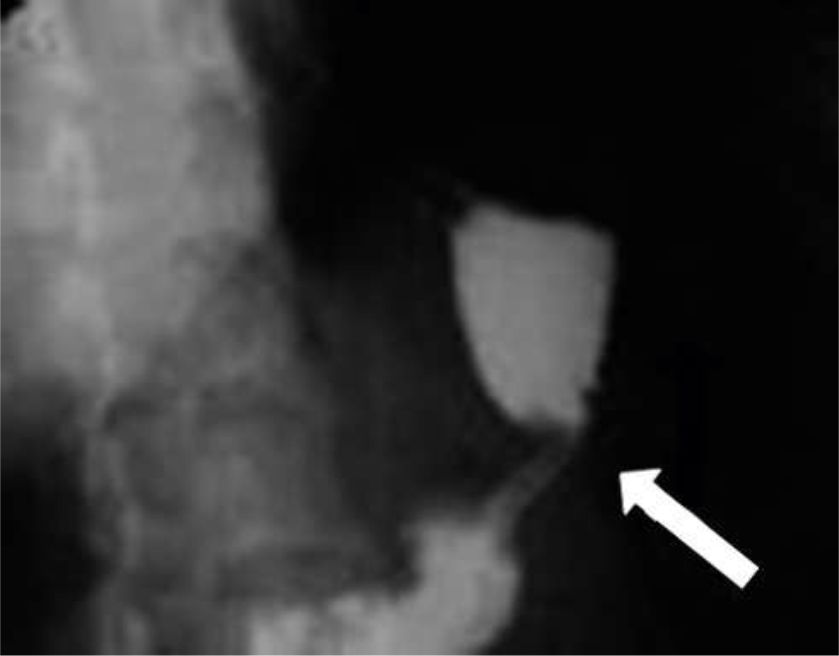

Figura 3

a) Corte axial

b) reconstrucción coronal de TC

sin medio de contraste endovenoso, donde se visualiza la GM con contraste positivo intraluminal (flechas curvas), fuga de contraste adyacente a la misma (flecha fina) y a nivel perihepático (flecha gruesa).

Según el tiempo de presentación se dividen en: precoces (1-4 días del postoperatorio), de etiología mecánica y tardías (más de 4 días), de etiología isquémica (6). Figura3 (a y b).